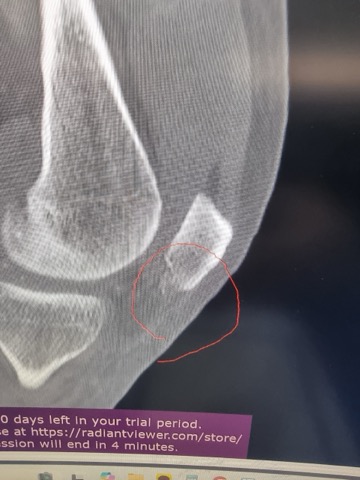

MRI, X-Ray 가지고 있는 사진 첨부했습니다.

무릎 골절, 견갑골 골절, 무릎인대 파열, 대퇴골의 골절, 경골 골절, 흉추 골절, 다발의 타박상, 다발의 찰과상, 뇌진탕